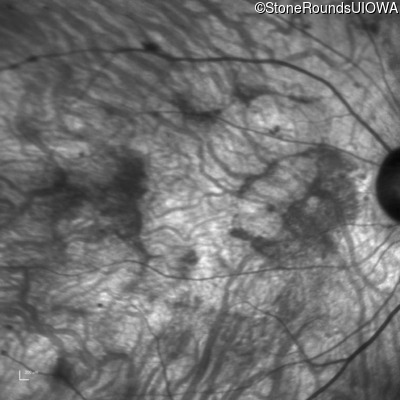

Infrared Fundus Photograph - Right - 20/200 +2

Exemplar